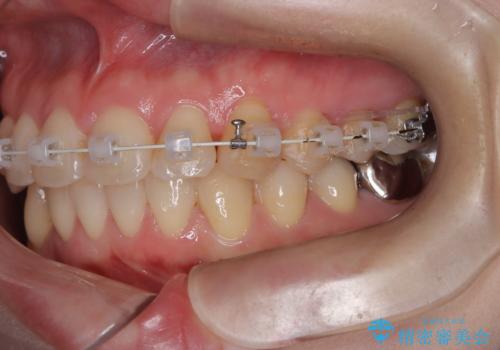

- 前歯の翼状捻転の改善を希望してこられた患者様です。

下顎の叢生はインビザラインで解決することがきましたが、上顎の捻転が完全には改善できなかったため、上顎は途中からワイヤーを用いて治療を行っています。

捻転の改善はインビザラインで苦手とするところですので、うまく治らない場合はワイヤーを提案しています。